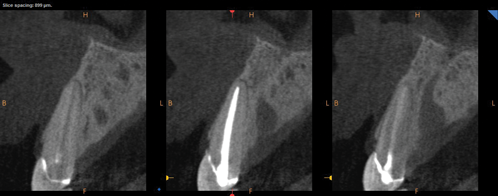

It has been established that the critical vascular supply to the periodontium and supportive alveolar bone is threefold22,23: (1) within the periosteum of the alveolar bone (Figure 1); (2) within the cancellous portion of the alveolar bone proper (Figure 1 and Figure 2); and (3) a vascular plexus within the PDL itself (Figure 2 and Figure 3). This further clarifies the fact that not only does the periodontal functional unit have components that are interdependent to each other, but critical vascular supply to the alveolar bone is composed of three unique units.

Fig 1. Photomicrographs illustrating vascular supply to the periodontium and supportive alveolar bone. Fig 1 shows the presence of a vascular network within the periosteum on the buccal aspect of the alveolar bone and within the cancellous aspect of the alveolar bone. Fig 2 demonstrates the vascular blood supply found within the PDL space adjacent to a tooth that has been sectioned in a buccolingual dimension. The blood supply to the cancellous bone and periosteum is also demonstrated in this section. (Images republished with permission of C.V. Mosby Co., from Keller GJ, Cohen DW. Oral Surg Oral Med Oral Pathol. 1955;8(5):539-542. Permission conveyed through Copyright Clearance Center, Inc.)

Figure 1